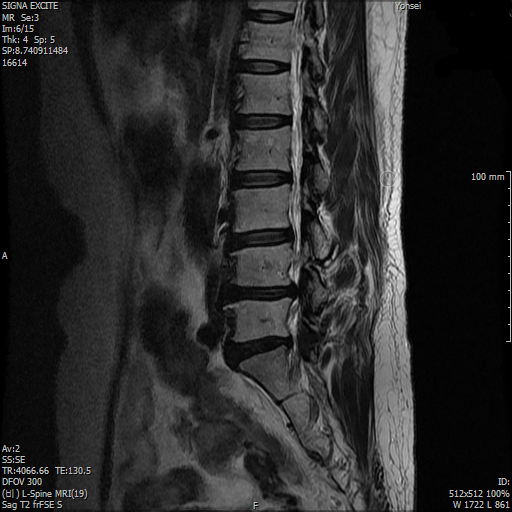

사진을 통해 보았을 때에는 허리협착증이라기 보다는 요추부 추간판 탈출증으로 보입니다. 즉, 4-5번 요추 사이의 디스크가 특히 뒤로 밀려나오며 척수신경을 누름으로 인해서 발생한 통증으로 보입니다. 급성 통증에 대해서는 진통제를 사용하여 조절하는 수밖에 없습니다.

1. 디스크가 튀어나와서 척수신경을 누르고 있습니다. 척수 내 공간이 좁아셔 신경을 압박하는 것을 전체적으로 척추관 협착증이라고 부릅니다.

요추 4/5 5/천추1이 안 좋아 보이며 그중 4/5번이 특히 안 좋아보입니다.